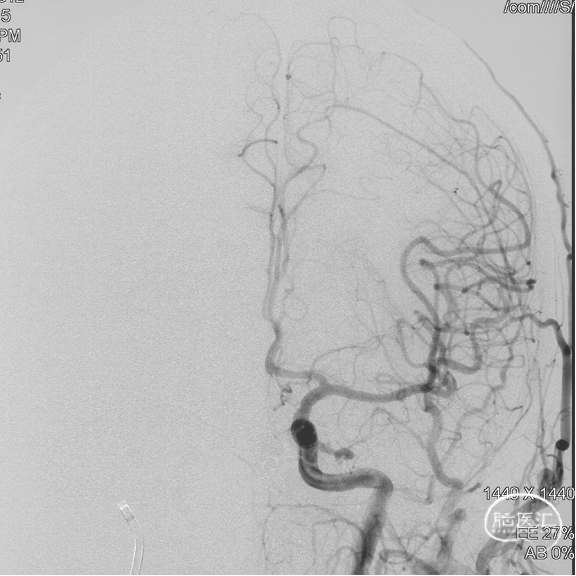

术前造影

双侧颈内动脉正侧位造影见前颅窝底硬脑膜动静脉瘘,双侧筛前动脉、筛后动脉向瘘口供血,通过皮层静脉向上矢状窦引流。

双侧颈外动脉正侧位造影见镰前动脉向瘘口供血。

左侧椎动脉正侧位造影未见明显异常。